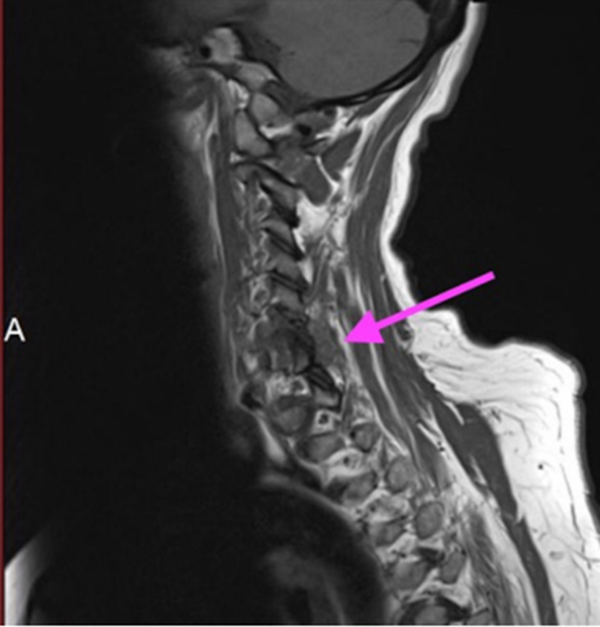

颈椎焦磷酸钙沉积病

C6/7椎板关节面不规则,骨髓信号减弱,椎周信号改变延伸至C6神经根的后侧和C7神经根的上侧

箭头显示在椎间后关节周围和左侧C6/7神经孔内的炎症过程增强